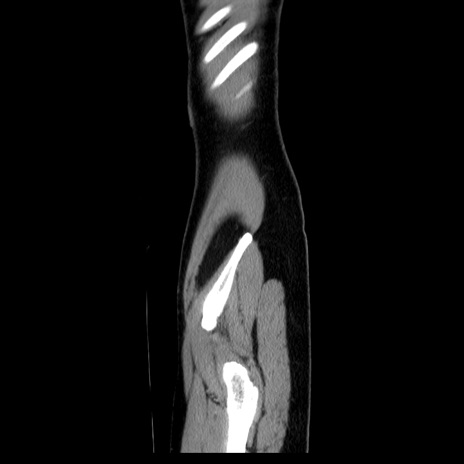

MRI(4日後)